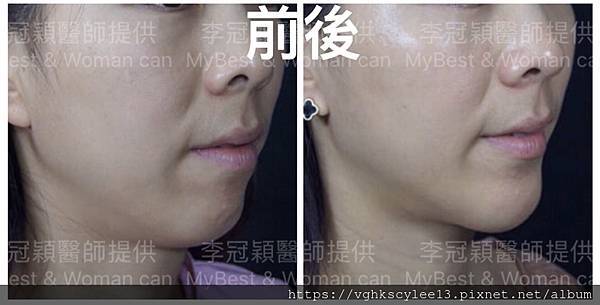

上 圖注射填下巴

下圖案例:下巴整形打造V型臉的效果(客製化goretex複合式假體)

案例:下巴整形(客製化goetex下巴假體)